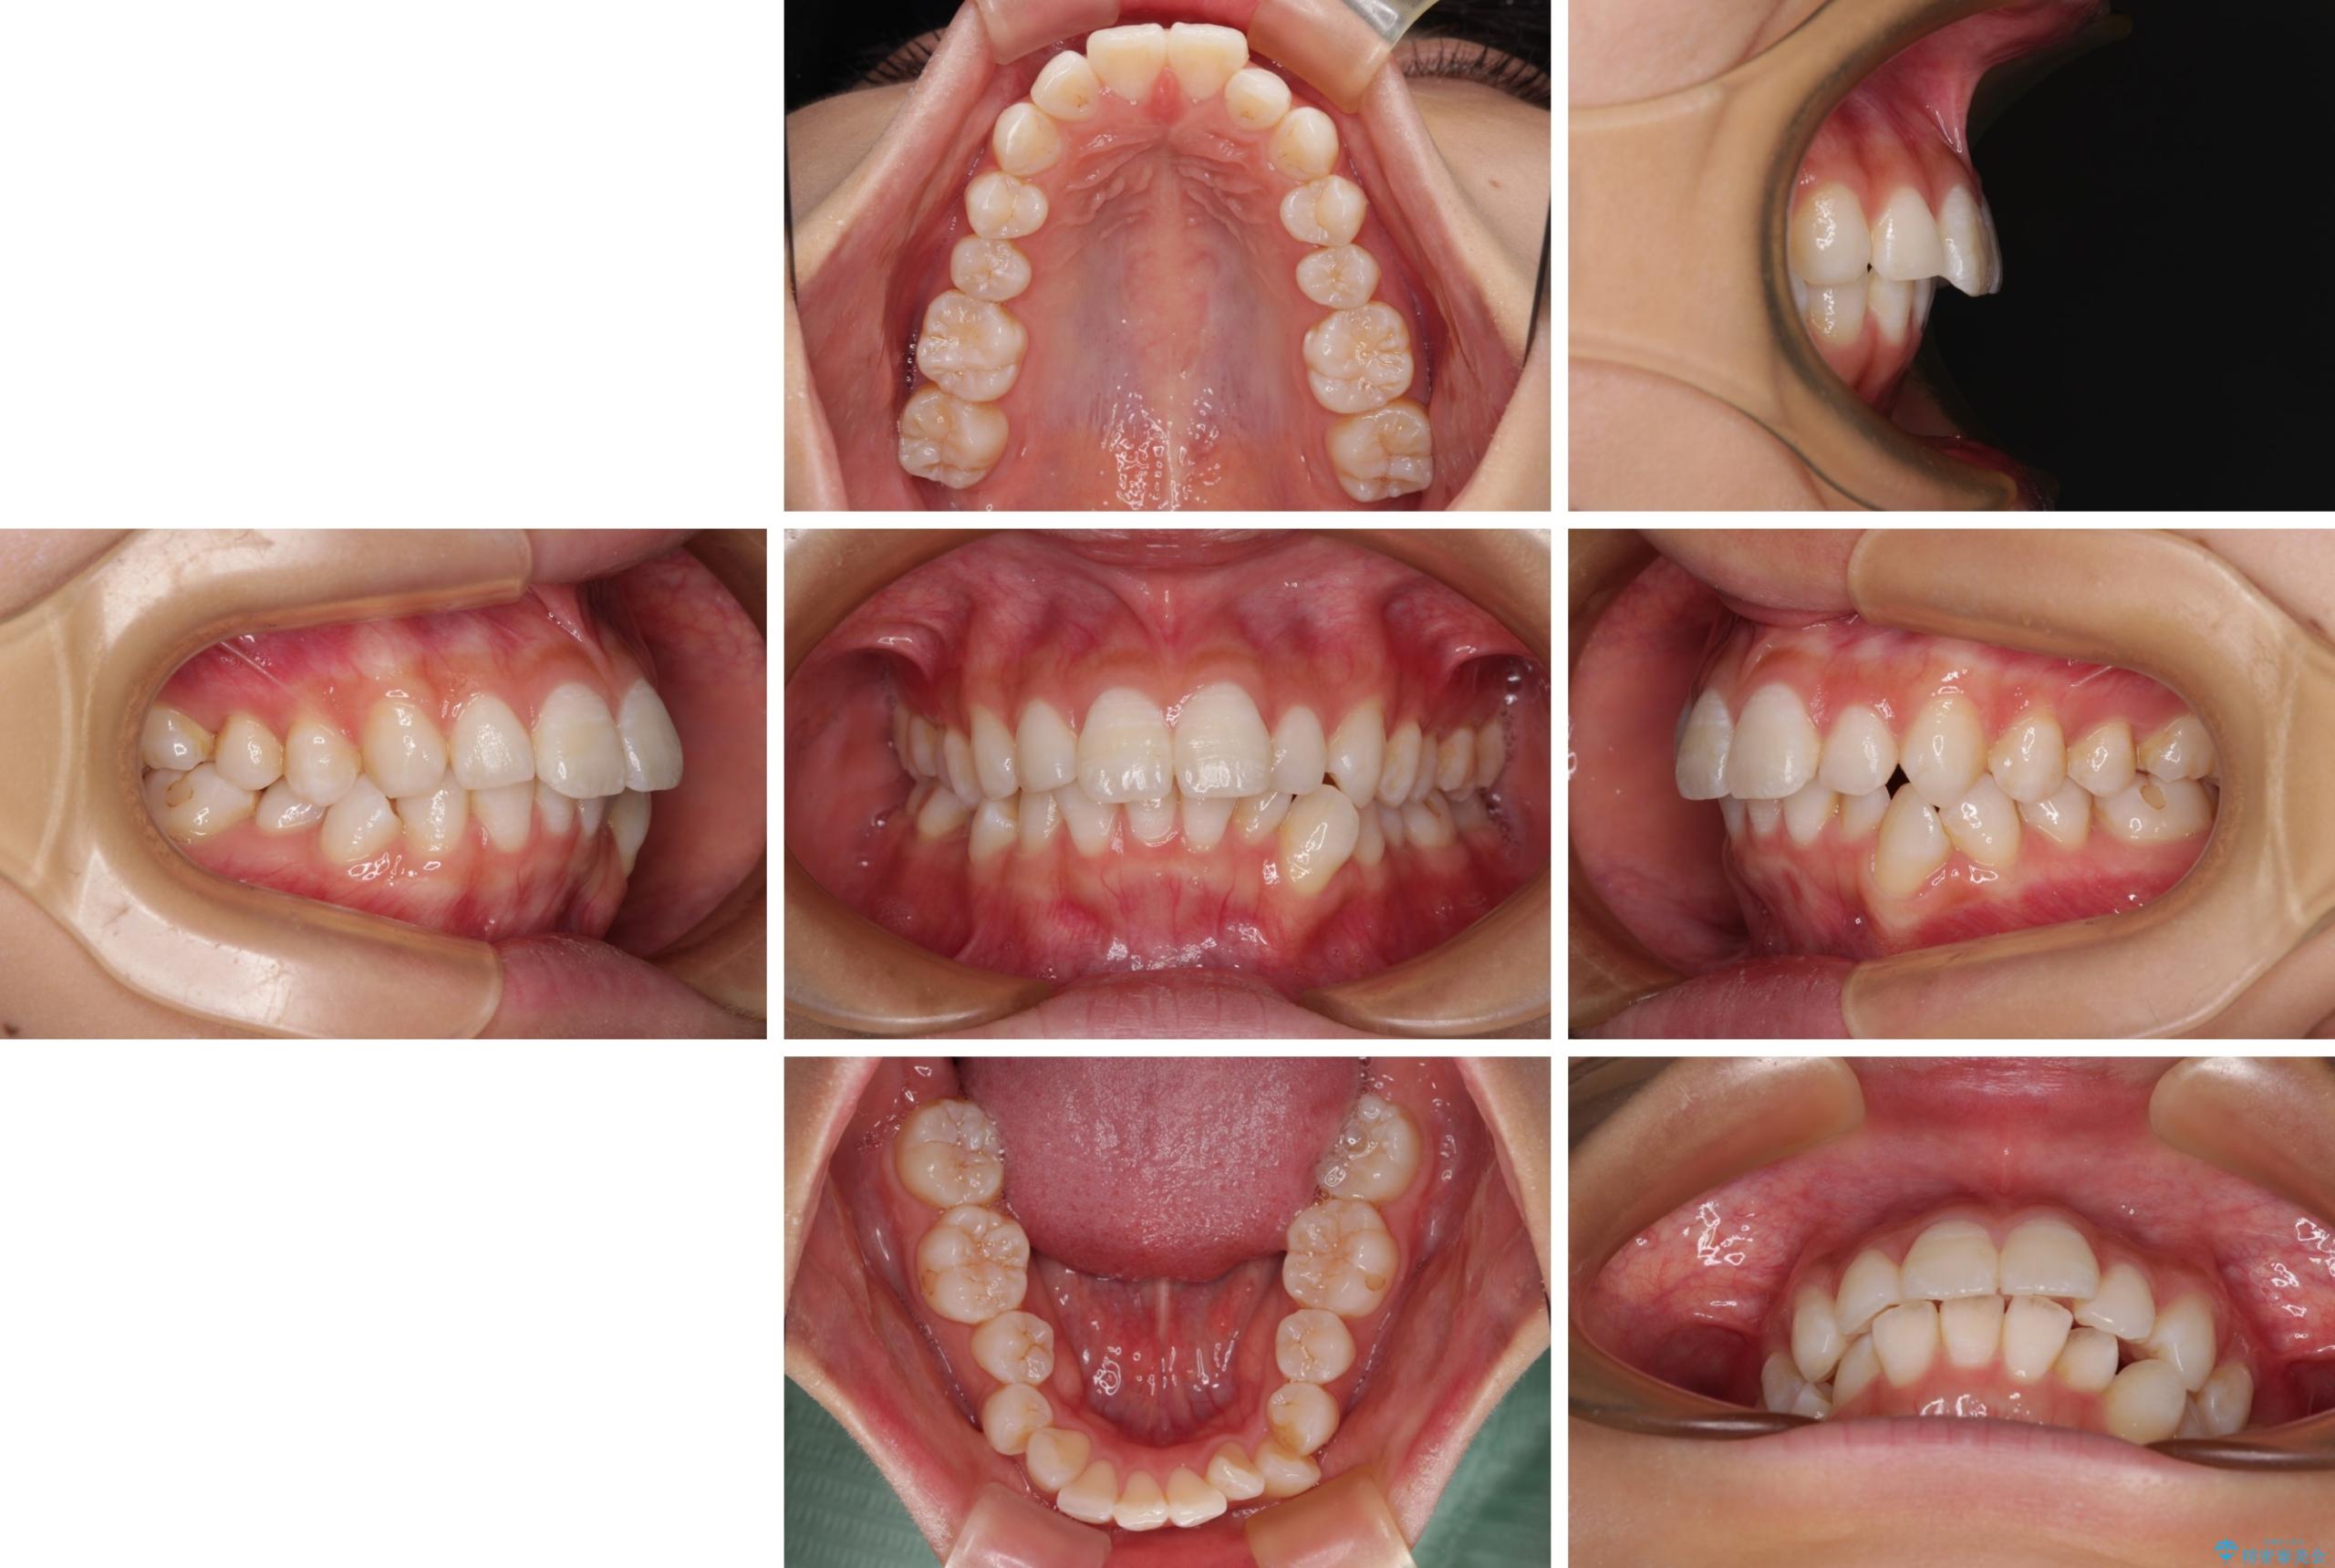

- 口を閉じたときに飛び出してしまう上顎前歯を気にして来院された患者様です。

下顎はデコボコが気になっていたため、上下左右第一小臼歯4本を抜去して、ワイヤー装置にて口元の突出感を改善するよう矯正治療を行うこととしました。

下唇に前歯が当たって跡が残ってしまう状態でしたが、スッキリとした口元に仕上げることができました。